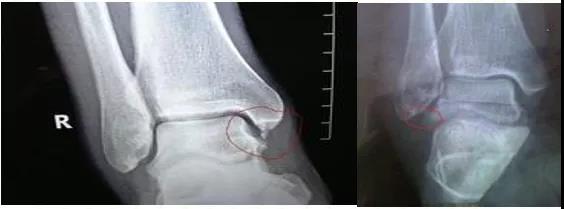

X线片:基本的辅助检查(应注意某些情况并非骨折)CT:能进一步检查隐匿性骨折或撕脱性骨折MRI:可检查肌腱、韧带的损伤肌骨超声:可代替或结合MRI检查软组织的损伤

X线

踝关节正位

踝关节侧位